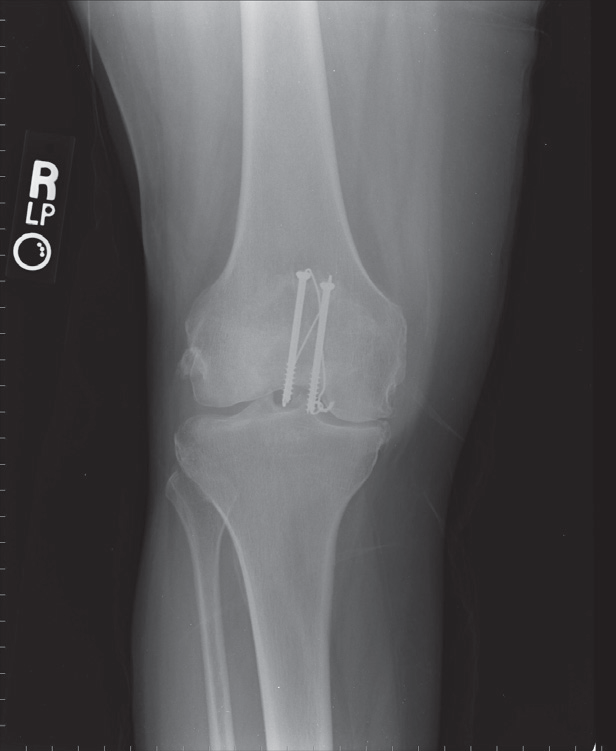

PATELLAFRAKTUR

Røntgen

i 2 planer.

Dislocerede

frakturer

Indlægges til åben osteosyntese.

Postoperativ rtg kontrol.